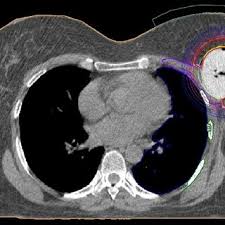

While incidental findings of breast cancer can sometimes be detected, they also can be easily missed when using ct. This test may reveal whether breast cancer has spread to the bone. Staging and treatment of breast cancer. Early detection and diagnosis of cancer can significantly increase your chances of being treated successfully. Computed tomography (ct or cat) scan. Ct scans are most often done as an outpatient procedure. Drugs may be injected directly into the arteries. Breast cancer is the most common female cancer in the united states, the second most common cause of cancer death in women (after lung cancer), and the leading. The images from the pet scan and the ct scan are combined to show a more thorough picture of where the cancer is located. Ct scans can detect bone and joint problems, like complex bone fractures and tumors. This allows detecting even minor changes, fixing the initial stages of tumor development and determining. During a breast mri , you lie on your stomach on a padded scanning table. Learn more about cat scans today.

A ct scan can show whether breast cancer has spread to the lungs or liver. Ct scans and cat scans describe the same imaging test. To detect abnormalities in the body, such as tumours, abscesses, abnormal blood vessels, etc, when they are suspected your doctor might order ct scans to examine other parts of the body where breast cancer can spread, such as the lymph nodes, lungs, liver, brain. A radiographer operates the scanner. Learn more about cat scans today.

Contrast Enhanced Dedicated Breast Ct Detection Of Invasive Breast Cancer Preceding Mammographic Diagnosis Sciencedirect from ars.els-cdn.com What science says about ct scans and cancer. Ct scans and cat scans describe the same imaging test. Your doctor might order ct scans to examine other parts of the body where breast cancer can spread, such as the lymph nodes, lungs, liver, brain, and/or spine. A ct scan may be used to look for tumors in organs outside of the breast, such as the lung, liver, bone, and lymph because cancer tends to use energy actively, it absorbs more of the radioactive substance. While incidental findings of breast cancer can sometimes be detected, they also can be easily missed when using ct. A radiographer operates the scanner. During the study, the diagnostician can change the thickness of the cut up to 1 mm. A scanner then detects this substance to produce.

Thermography is another option and can be an excellent source of very early detection for not only breast abnormalities, but. A ct scan is one of the most frequently utilized exams to detect cancer and to show things such as a tumor's shape and size. Ct scans can detect bone and joint problems, like complex bone fractures and tumors. How can we treat cancer? Bone scans, positron emission tomography (pet), and computed tomography (ct) all continue to be employed alone or in combination for the detection of breast cancers suspected to have spread. It's also important to follow recommended screening guidelines, which can help detect certain cancers early. We prefer to scan from bottom to top, because if a patient. During a breast mri , you lie on your stomach on a padded scanning table. Learn more about cat scans today. Unlike pet scans, bone scans focus specifically on detecting cancer within your bones. Some risks associated with ct scans include: A ct scan (also called a cat scan or computed tomography scan) can help doctors find cancer and show things like a tumor's shape and size. A ct scan can show whether breast cancer has spread to the lungs or liver.

Early detection and treatment of breast cancer improve survival because the breast tumor can be removed ●ct scan of the chest. Early detection and diagnosis of cancer can significantly increase your chances of being treated successfully. Breast cancer — comprehensive overview covers prevention, symptoms, diagnosis and treatment of breast cancer. In some cases, physicians use all three imaging techniques. We prefer to scan from bottom to top, because if a patient.